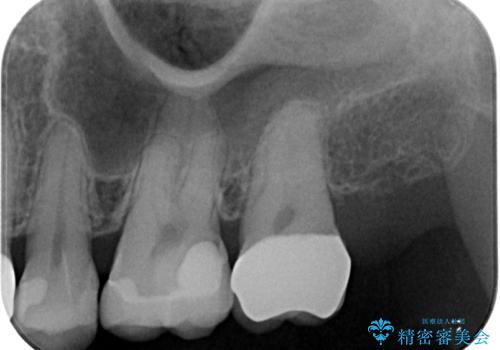

レントゲン写真より、奥歯2本に大きなむし歯があることが分かりました。

手前の歯はセラミックインレーで、奥の歯はオールセラミッククラウンにて治療を行うこととしました。